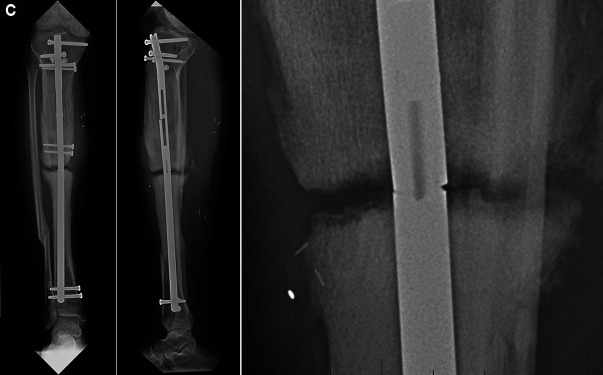

Case description: A 42-year-old male presented for complex right tibia reconstruction following a type IIIB open tibia fracture with a 92-mm bone defect. The bone defect was initially managed with an all-internal bone transport nail system (PRECICE bone transport). At the 13-month follow-up, the patient presented with a broken lengthening nail, varus limb deformity, and nonunion at the docking site. The nail components were extracted sequentially, and a burr hole was created in the distal segment of the nail through the nonunion site to facilitate removal. The residual varus deformity and tibial shaft nonunion were managed with a hexapod frame.

Conclusion: The IMLN was successfully removed without compromising limb reconstruction. By sequentially removing the components of the nail and altering the distal portion of the implant through the nonunion site, safe removal of the implant without further bone loss was achieved.